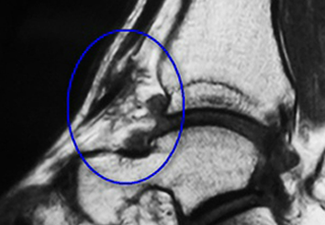

Imagenes:

Sindrome partes blandas.